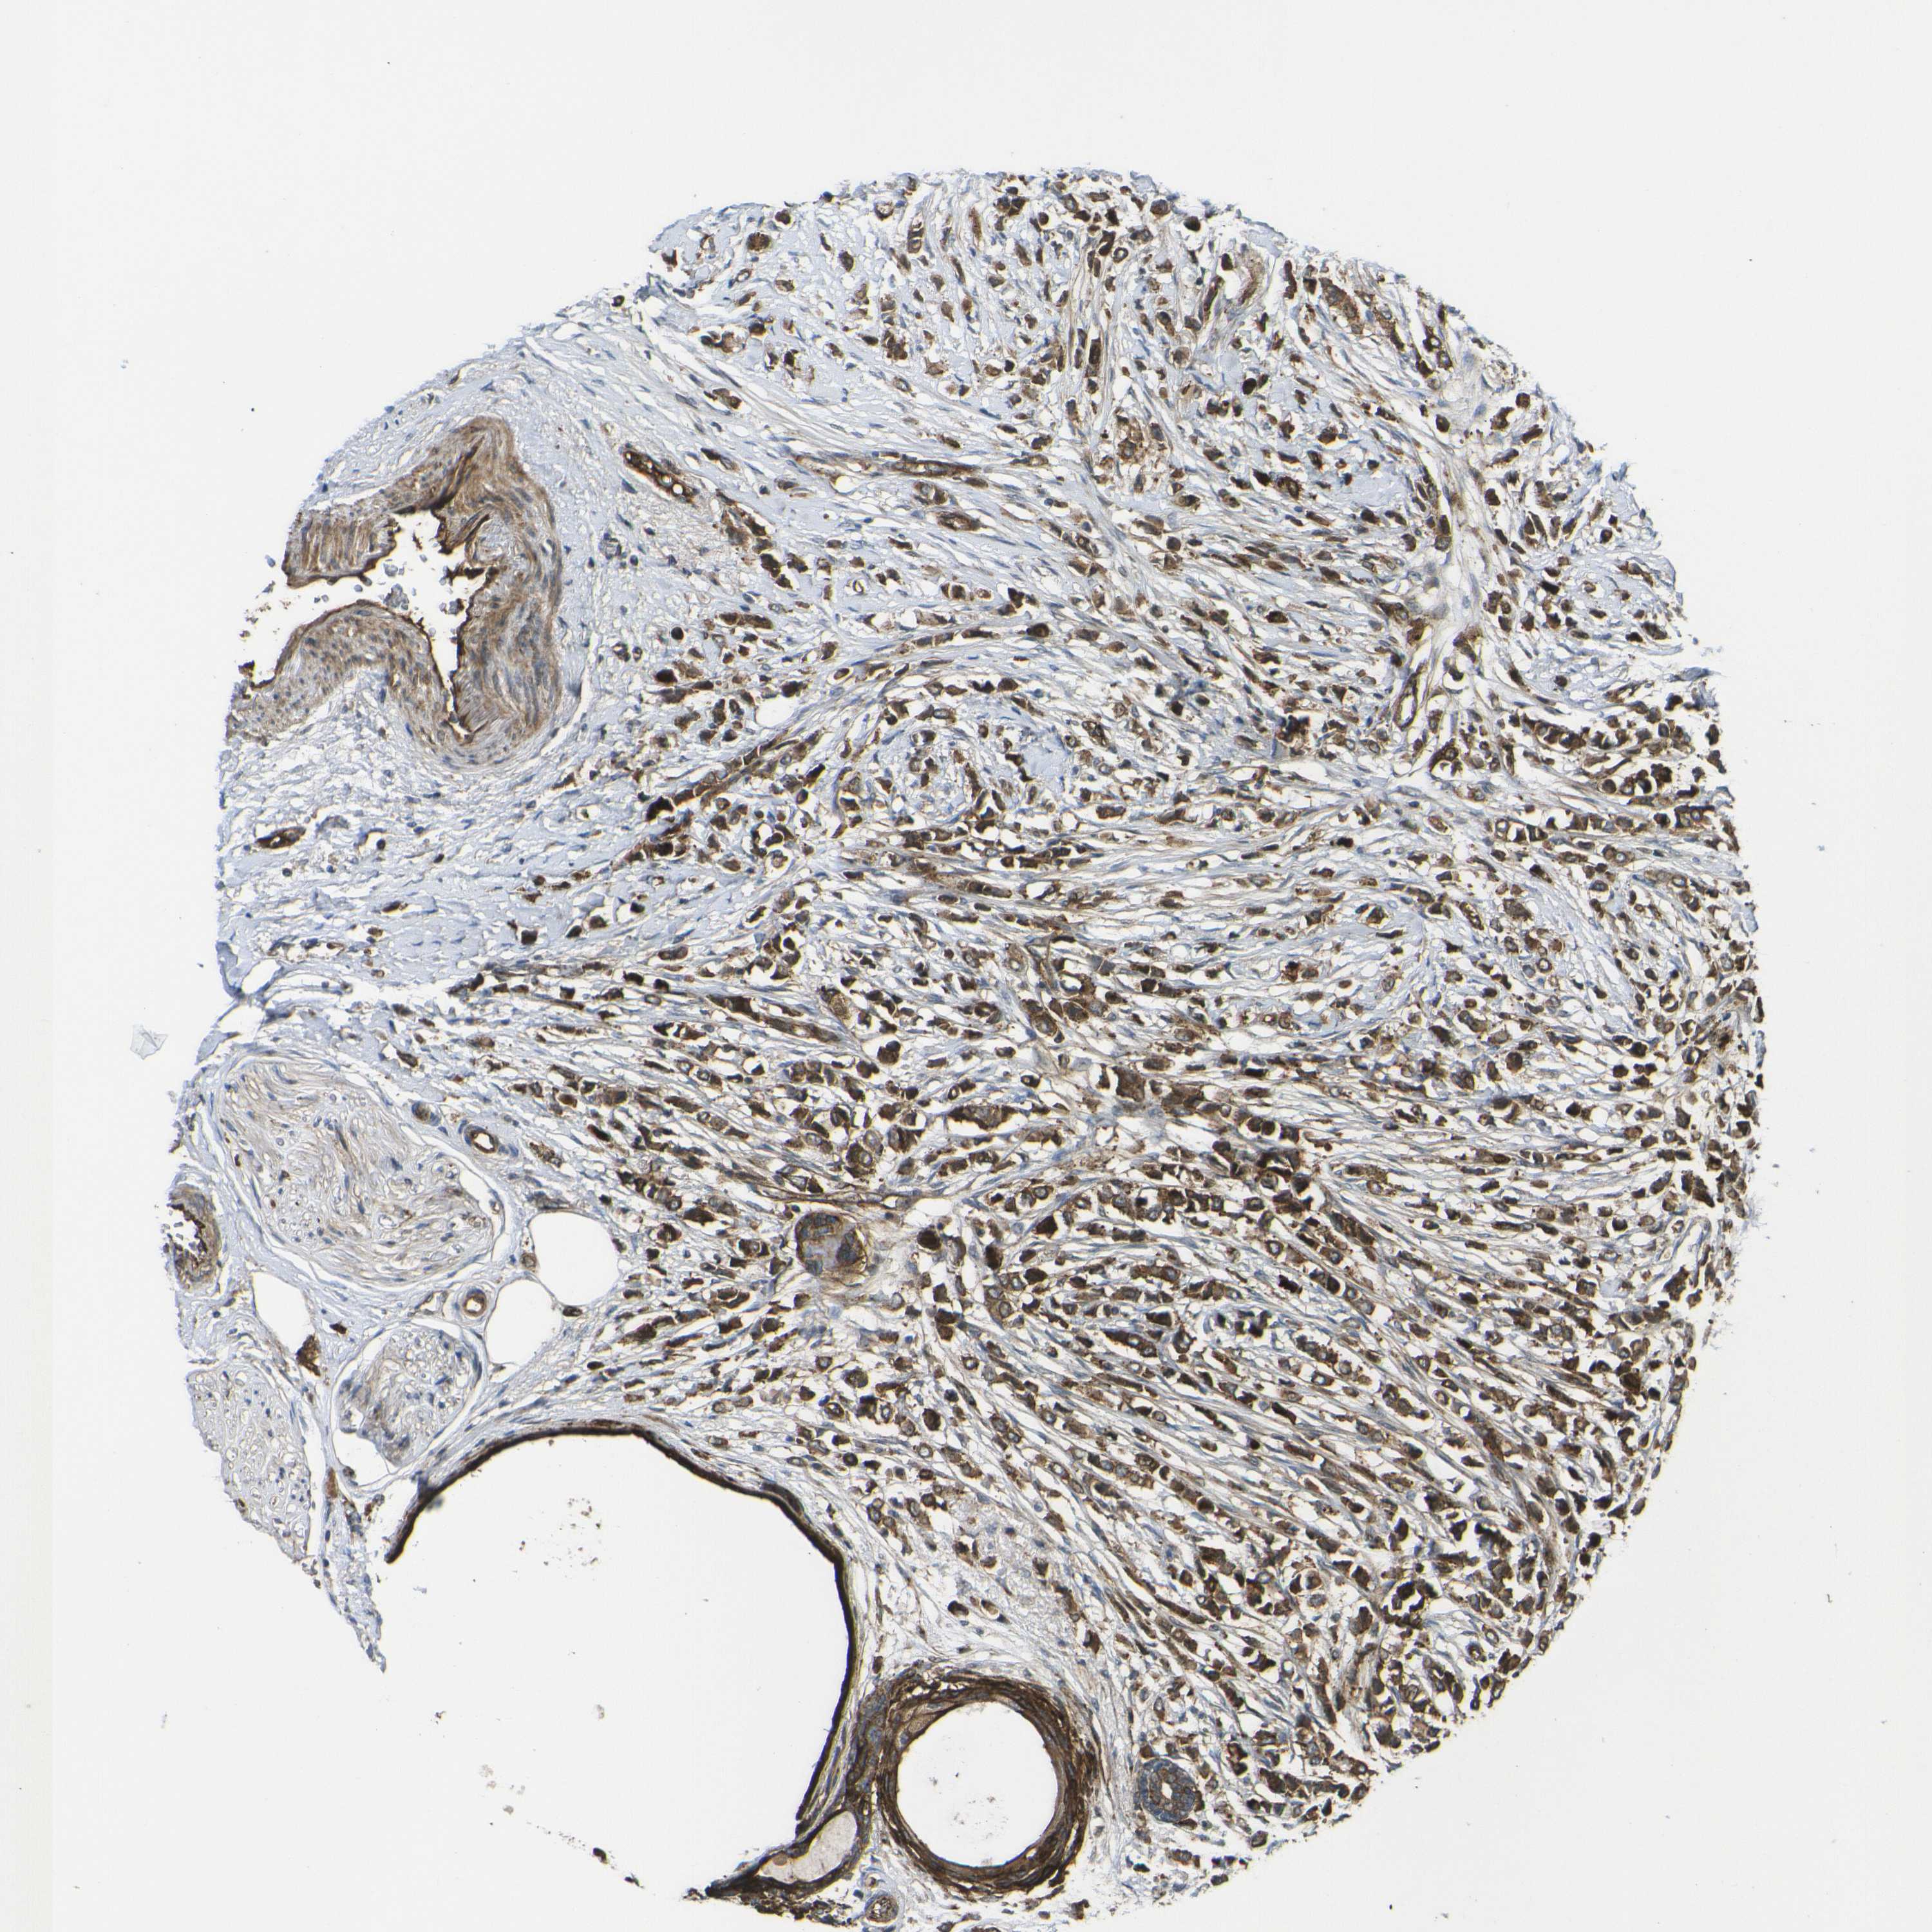

CANCER BREAST CANCER Show tissue menu

BRCA TCGA BRCA VALIDATION PROTEIN EXPRESSION